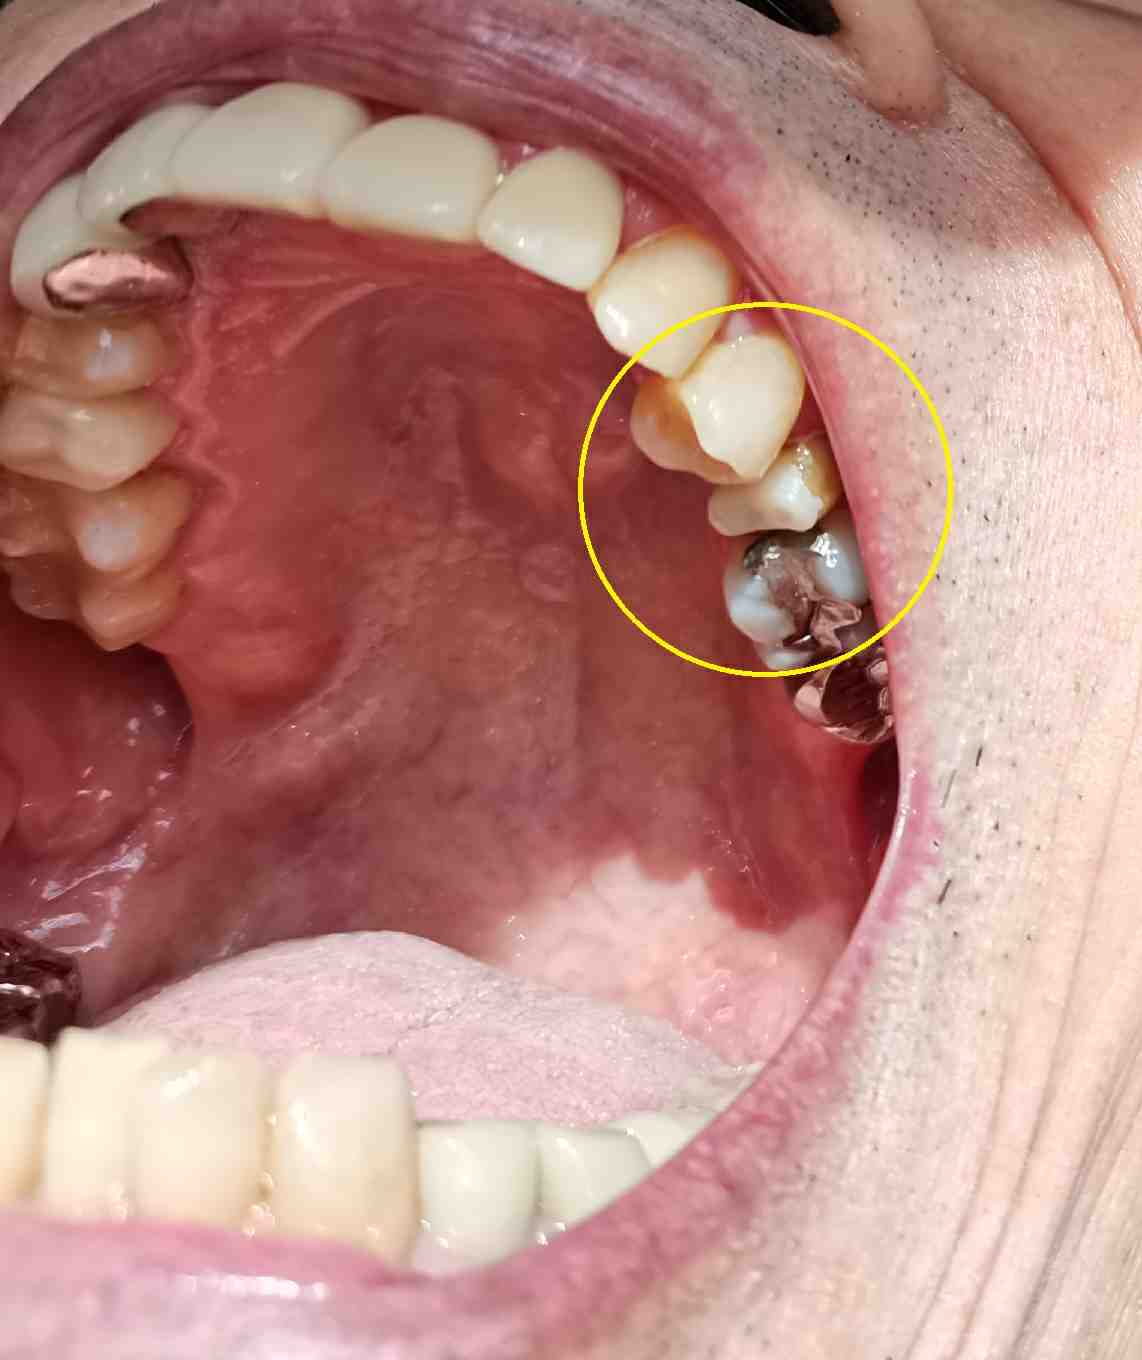

左上5番に土台をはめた。

(次回、型取り)

今日は土台をはめただけ。